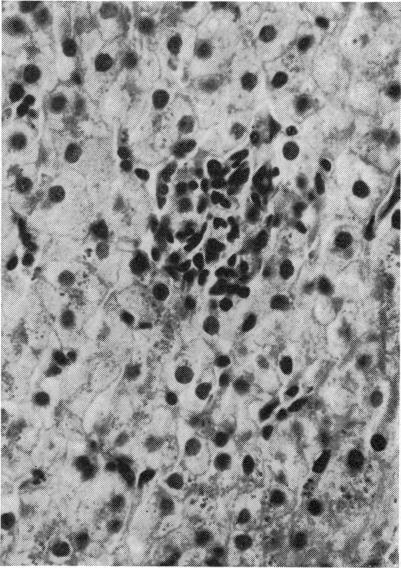

There have been no published reports on the liver of patients with haemoglobin H disease. In 11 Chinese patients studied (six male and five female) with haemoglobin H disease hepatic function and histology were studied. Liver function was normal in all cases; however, the gamma globulin level was raised in four cases, the increase being mainly in IgG in all cases and IgA in six cases. Liver histology showed that one case had portal cirrhosis, six cases mild fibrosis, and four cases no fibrosis. Haemosiderosis, mainly in the parenchymal cells of the peripheral lobules, was mild in one case, moderate in four, and severe in the remainder of the cases.

关于血红蛋白H病患者的肝脏,尚无已发表的报告。对11例血红蛋白H病中国患者(6例男性和5例女性)进行了肝功能和组织学研究。所有病例肝功能均正常;然而,4例γ球蛋白水平升高,所有病例中升高主要为IgG,6例为IgA。肝脏组织学显示有1例为门脉性肝硬化,6例为轻度纤维化,4例无纤维化。含铁血黄素沉着症主要见于外周小叶的实质细胞,1例为轻度,4例为中度,其余病例为重度。